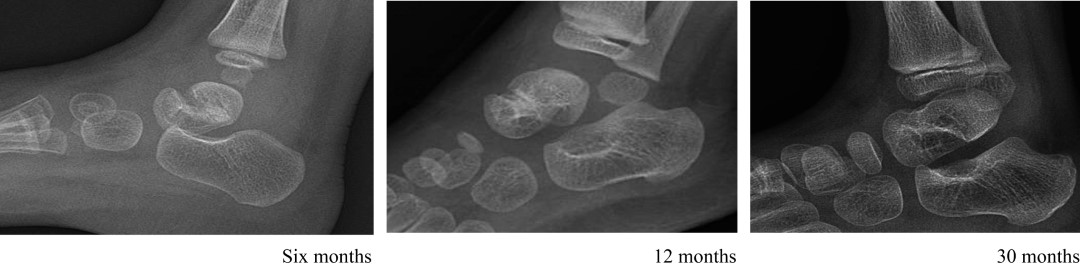

La osteomielitis causada por el bacilo de Calmette-Guérin (BCG) es una complicación poco frecuente de la vacunación con Mycobacterium bovis. Las lesiones suelen localizarse en la metáfisis o epífisis de los huesos largos, pero rara vez afectan el pie. En este informe se describen dos casos de osteomielitis por BCG que afectaban el astrágalo en lactantes de 13 y ocho meses de edad. La osteomielitis por BCG debe sospecharse en niños menores de dos años con osteomielitis insidiosa, acompañada de hallazgos característicos en las imágenes.

Figura 1

Figura 2

Figura 3

Figura 4

Figura 5

Figura 6

Figura 7